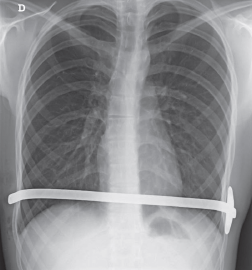

Imágenes y Cirugía

Natalia González Alcolea, María Dolores Chaparro Cabezas, Félix Martínez Arrieta, Victor Sánchez Turrión